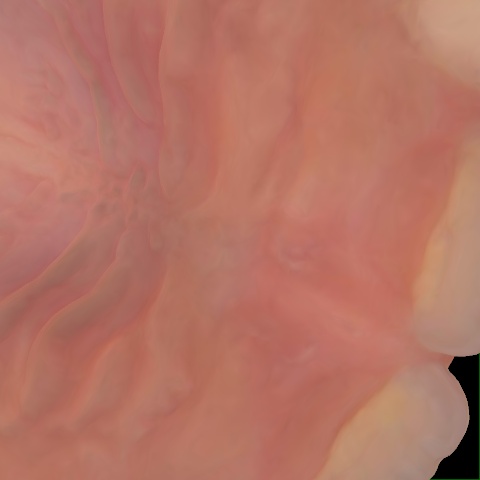

Incorrect Quality Level

The reference annotation for this image is

None

.

Please select the correct quality level.

Annotated as "Good"